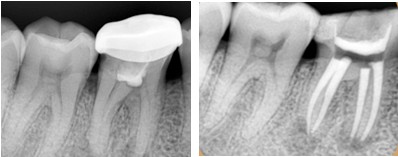

一般情况下,我们牙齿的蛀牙会经历这几个过程:大家看下图↓↓↓

一般情况下到了深龋,并伴有疼痛,说明蛀牙已经影响到牙髓腔了,如果牙髓被感染了就要进行根管治疗。并不是医生想要唬你。如果还没到达深龋,没有感染牙神经,一般只需要进行去腐后常规补牙即可。

牙齿做根管治疗后补牙多少钱一颗,为什么要做根管治疗不能直接补牙